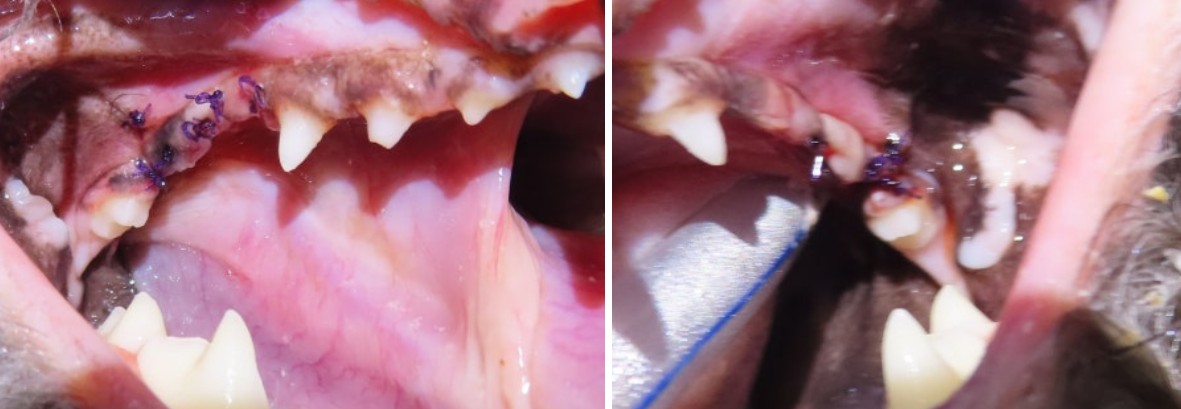

강북구 쌍문동 동물병원 비아츠에서는 양측 상악 M1을 치근 분리 후 단계적으로 제거하는 방식으로 발치를 진행했습니다.

대구치는 뿌리가 2개로 나뉘어 있고 치조골 소실이 동반된 경우 난도가 높은 치아입니다.

치근을 하나씩 분리하여 제거하고 잔존 치조골을 정리한 뒤 조직을 긴장 없이 봉합하는 방식으로 마무리했습니다.